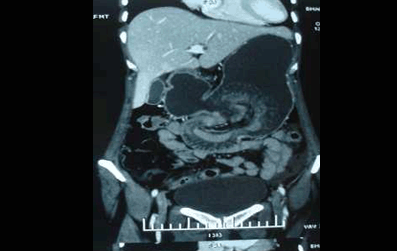

Figure 1: CT scan of abdomen showing dilated stomach with intragastric non-homogeneous mass compatible with small bowel loops. (Page 9)